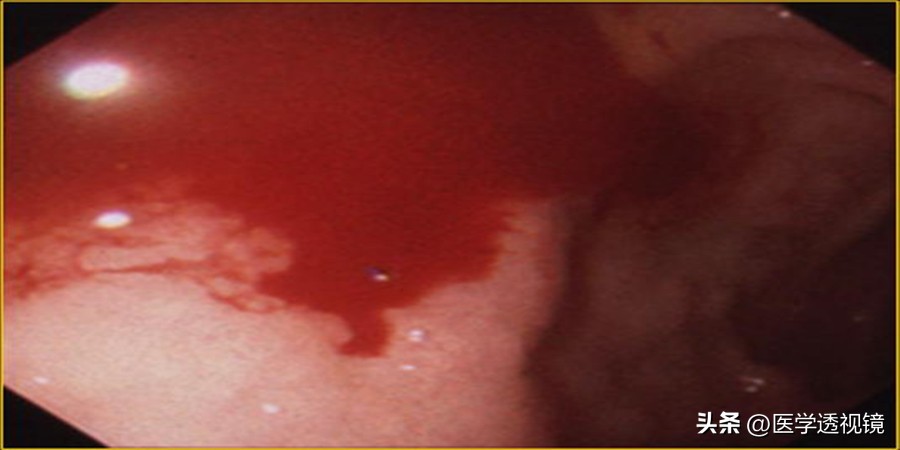

十二指肠溃疡出血

确诊胃十二指肠溃疡主要行胃镜+黏膜活检,这是确诊消化性溃疡的首选方法,其目的在于: ①确定有无病变、部位及分期;②鉴别良恶性; ③评价治疗效果; ④对合并出血者给予止血治疗。